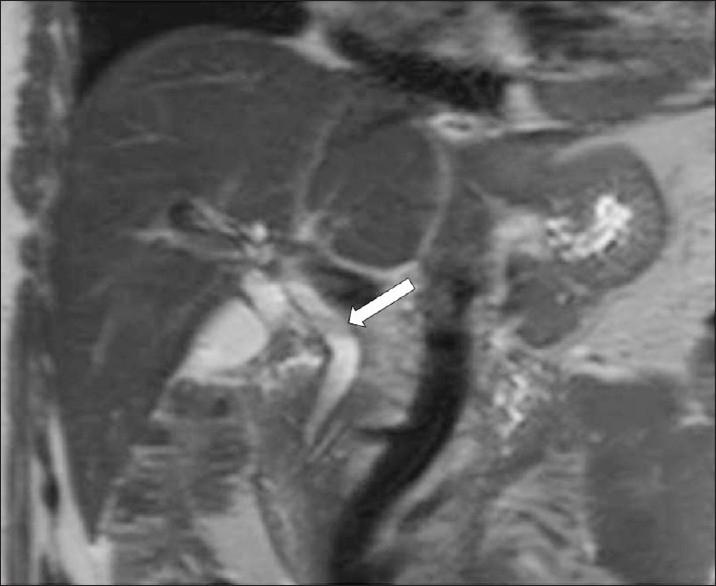

Fascioliasis refers to a zoonosis caused by Fasciola hepatica, a trematode infecting herbivores, but also occurs in humans who ingest the metacercaria found in fresh water plants. Infection in humans is common in developing countries and is also not uncommon in Europe. Diagnosis of this infection is difficult, as the history and symptoms are nonspecific and stool analysis for eggs is negative until the disease is in an advanced state by when the parasite has reached the biliary system. The clinical course consists of two phases; first a hepatic parenchymal phase in which immature larvae invade the liver parenchyma, followed by a ductal phase characterized by the excretion of larvae into the bile ducts. Parenchymal Phase: Ultrasonography (US) findings are nonspecific in this early phase. Computerized tomography (CT) may demonstrate subcapsular low attenuation regions in the liver. Magnetic Resonance imaging (MRI) can also be utilized to establish liver parenchymal involvement, and is better than CT in characterizing hemorrhagic lesions, as well as identifying more lesions relative to CT. Ductal Phase: US examination is most useful at this stage, with its ability to demonstrate the live movement of the worms within the dilated ducts. A CT demonstrates dilated central biliary ducts with periportal tracking, whereas, mild ductal dilatation is poorly appreciated under MRI. Therefore, familiarity with the multimodality imaging features of fascioliasis, in combination with an available confirmatory enzyme-linked immunoassay, would be most helpful for early diagnosis.

肝片吸虫病是一种由肝片吸虫引起的人畜共患病,这种吸虫感染食草动物,但人类摄入淡水植物中的囊蚴后也会感染。在发展中国家,人类感染这种疾病很常见,在欧洲也并不罕见。这种感染的诊断很困难,因为病史和症状不具有特异性,而且在疾病发展到晚期寄生虫进入胆道系统之前,粪便虫卵分析一直呈阴性。临床病程包括两个阶段:首先是肝实质期,未成熟幼虫侵入肝实质,随后是导管期,其特征是幼虫排入胆管。实质期:在此早期阶段,超声检查(US)结果不具有特异性。计算机断层扫描(CT)可能显示肝脏包膜下低密度区域。磁共振成像(MRI)也可用于确定肝实质受累情况,在表征出血性病变以及相对于CT识别更多病变方面比CT更好。导管期:US检查在这个阶段最有用,它能够显示扩张胆管内虫体的活动。CT显示中央胆管扩张并伴有门静脉周围条索状影,而在MRI下轻度胆管扩张不易被察觉。因此,熟悉肝片吸虫病的多模态影像学特征,并结合可用的确诊酶联免疫测定,对早期诊断最有帮助。